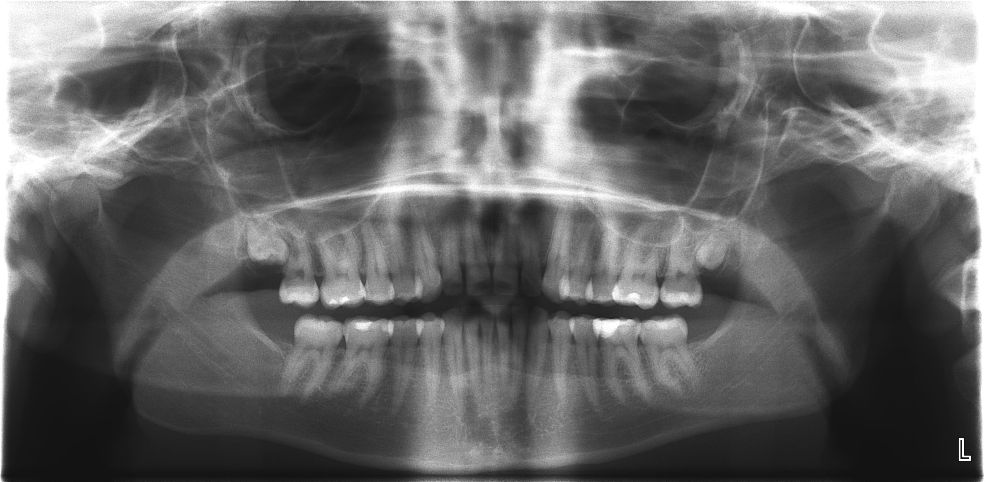

Как и зачем делают панорамный рентгеновский снимок зубов

На одном снимке получается совместное изображение нижней и верхней челюсти. Круговое изображение показывает состояние

Рентген ОПГ — зачем делается, что показывает

Ортопантомография (рентген ОПГ, ОПТГ, панорамный снимок зубов) – разновидность диагностического рентгенологического исследования. Этот метод